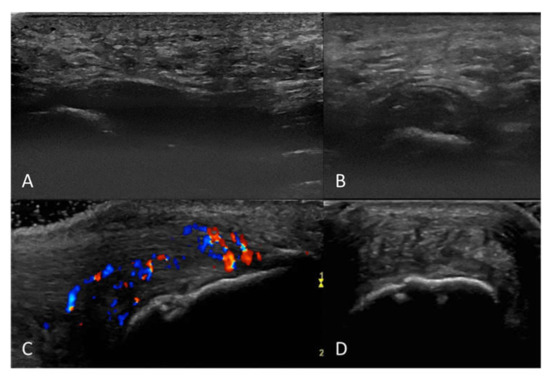

2.2. Ultrasound Examination and Scoring